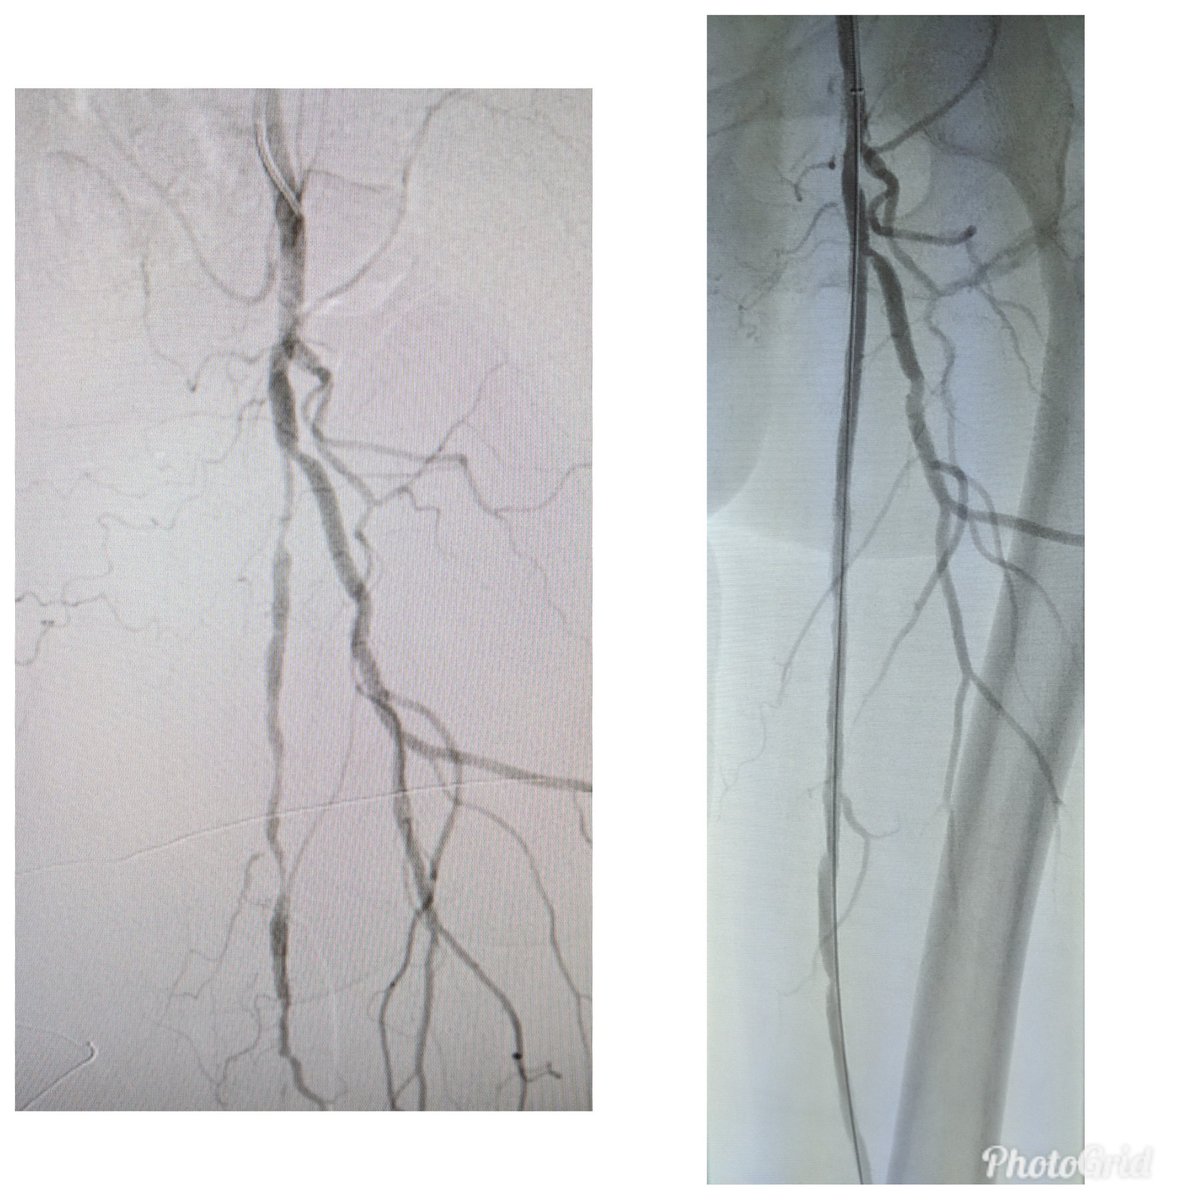

Reconstruction of below knee occlusions are so satisfying. #pad @CLIFightersBot #stopthechop @AMPSymposium #commandWire